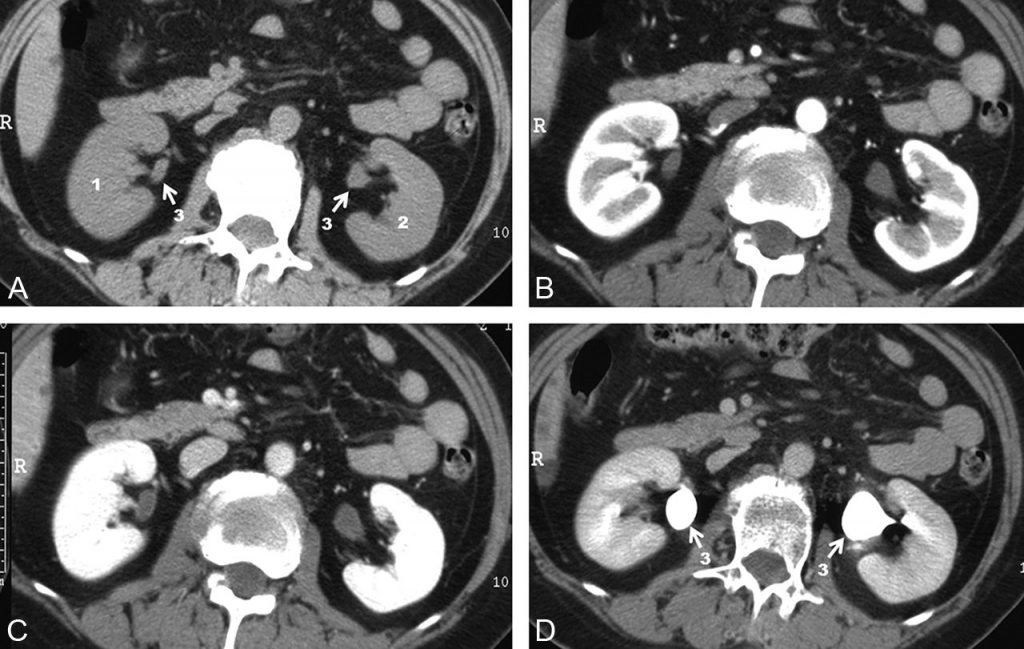

Fig. 19.8. Scanner rénal sans et avec injection intraveineuse de produit de contraste iodé (120 ml de produit non ionique dosé à 350 mg d’iode).

Coupes passant par le hile des reins avant injection (A), après injection à la phase artérielle (ou corticomédullaire), 40 secondes après injection (B), à la phase néphrographique 90 secondes après injection (C) et à la phase excrétoire 3 minutes après injection (D).

1. Rein droit. 2. Rein gauche. 3. Pelvis rénaux.

Rehaussement artériel (notamment de l’aorte) et du cortex rénal à la phase corticomédullaire (B). Rehaussement homogène du parenchyme rénal (cortex et médullaire) à la phase néphrographique (C). Opacification de l’appareil excréteur avec remplissage opaque des pelvis rénaux (3) et décroissance de la densité du néphrogramme parenchymateux à la phase tardive excrétoire (D).

Source : CERF, CNEBMN, 2022.